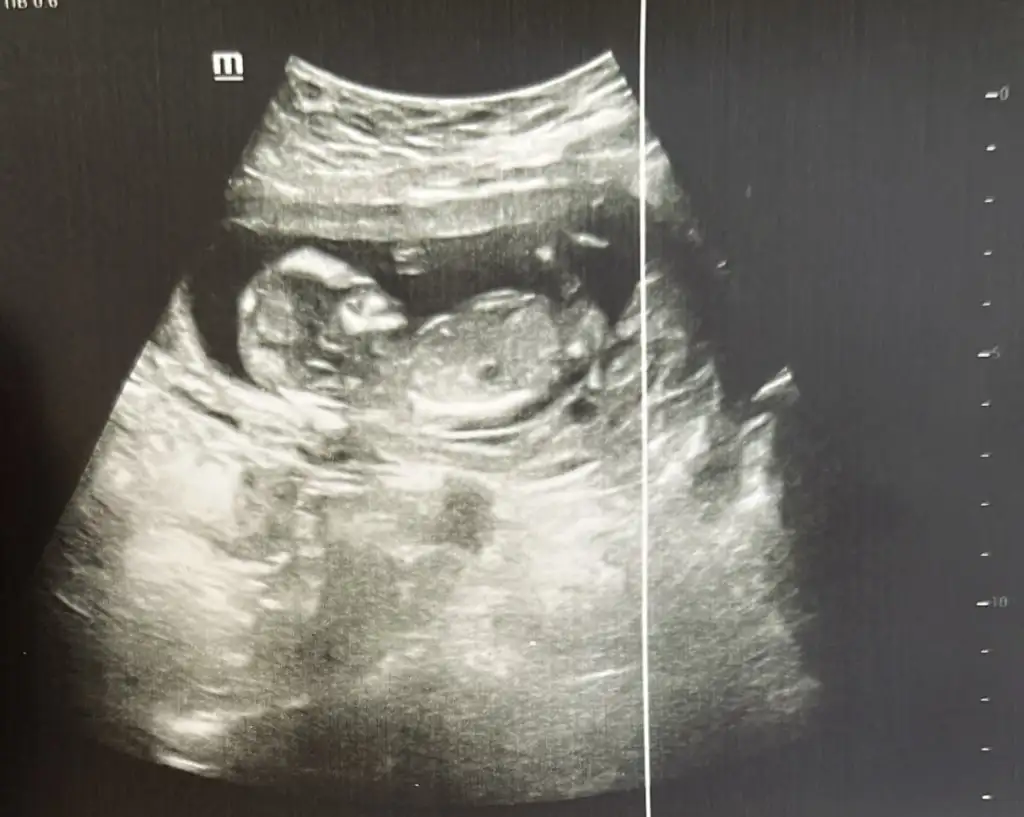

Pek anlamam canım ama aynı benim minnoş kızıma benziyoKızlar bugün 13+0 oldum. İkili test verdim. Doktor çok profesyoneldi. Devlet hastanesinde erken söylemiyorlar diye sormaya da utandım. Sizce neye benziyo? Ctesi ilk bebeğimin doğumunu yaptıran doktora randevum var orda öğrenirim gibi geliyor ama yorumlarınızı merak ettim.